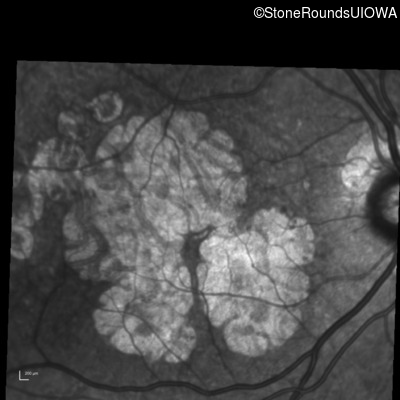

Infrared Fundus Photograph - Right - 20/25

Exemplar